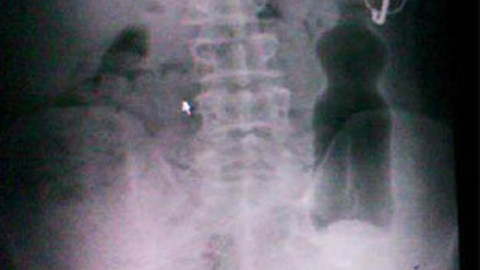

Edirne'de, duş yapmak için girdiği banyoda ayağı kayınca pet şişenin üzerine düştüğünü söyleyen 50 yaşındaki S.Y. yakınları tarafından hastaneye kaldırıldı. Makattan girerek ince bağırsaklara kadar ulaşan 330 mililitrelik pet şişe, ameliyatla çıkarıldı.

Edirne'de oturan 50 yaşındaki erkek S.Y., iddialara göre duş yapmak için banyoya girdi. Üzerindeki kıyafetleri çıkardığı sırada dengesini kaybettiği belirtilen S.Y. düştü ve o sırada yerde bulunan 330 mililitrelik pet şişenin üzerine oturdu. Acı içinde kıvranan S.Y.'nin çığlıkları üzerine banyoya gelen yakınları, hemen Trakya Üniversitesi Tıp Fakültesi acil servisine getirildi. Burada gömlek cebinde kalan gözlüğü ile birlikte röntgen filmi çekilen S.Y.'nin üzerine düştüğünü iddia ettiği pet şişenin ince bağırsaklara kadar ulaştığı ve o bölgedeki kolonlarda kaldığı görüldü.

Genel Cerrahi servisinde ameliyata alınan S.Y.'nin makatından girdiği tespit edilen pet şişe, yapılan operasyonun ardından karnı kesilerek ameliyatla çıkarıldı. 1 gün hastanede müşade altında tutulan S.Y., daha sonra hastaneden taburcu edildi.